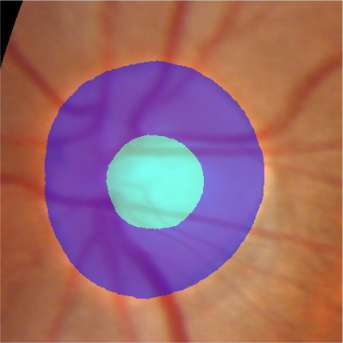

Glaucoma is the second leading cause of blindness and is the leading cause of irreversible blindness disease in the world. Early screening for glaucoma in the population is significant. Color fundus photography is the most cost effective imaging modality to screen for ocular diseases. Deep learning network is often used in color fundus image analysis due to its powful feature extraction capability. However, the model training of deep learning method needs a large amount of data, and the distribution of data should be abundant for the robustness of model performance. To promote the research of deep learning in color fundus photography and help researchers further explore the clinical application signification of AI technology, we held a REFUGE2 challenge. This challenge released 2,000 color fundus images of four models, including Zeiss, Canon, Kowa and Topcon, which can validate the stabilization and generalization of algorithms on multi-domain. Moreover, three sub-tasks were designed in the challenge, including glaucoma classification, cup/optic disc segmentation, and macular fovea localization. These sub-tasks technically cover the three main problems of computer vision and clinicly cover the main researchs of glaucoma diagnosis. Over 1,300 international competitors joined the REFUGE2 challenge, 134 teams submitted more than 3,000 valid preliminary results, and 22 teams reached the final. This article summarizes the methods of some of the finalists and analyzes their results. In particular, we observed that the teams using domain adaptation strategies had high and robust performance on the dataset with multi-domain. This indicates that UDA and other multi-domain related researches will be the trend of deep learning field in the future, and our REFUGE2 datasets will play an important role in these researches.